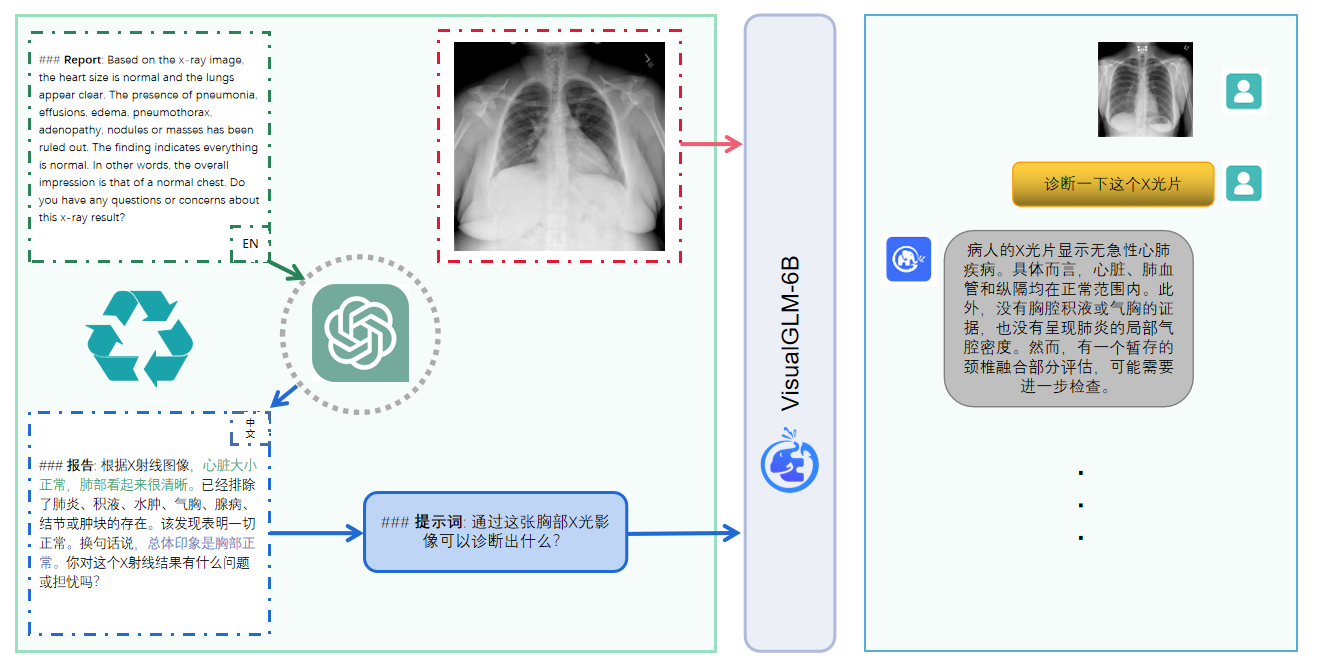

## 效果展示

*以下效果来自于**低质量**的数据训练和权重

影像诊断:

|X光影像|诊疗报告(医生)|XrayGLM|

|:-|:-|:-|

||根据X射线图像,心脏大小正常,肺部看起来很清晰。已经排除了肺炎、积液、水肿、气胸、腺病、结节或肿块的存在。该发现表明一切正常。换句话说,总体印象是胸部正常。|X光片显示,心脏大小正常。肺部没有气胸或胸腔积液的证据。骨骼结构看起来没有任何异常。总的来说,X光片表明没有发现急性心肺疾病的迹象。|

||X光图片显示没有扭曲的区域、可疑的骨质不透明度或胸腺积液。心脏大小轻微增大,但非常稳定。此外,没有气胸的证据,肺野也正常。总体来说,X光片显示没有急性心脏异常,但要注意轻微的心脏扩大。|X光片显示,心脏大小正常。肺部和纵隔轮廓清晰,没有气胸或胸腔积液的证据。骨骼结构完整,没有任何急性异常。|

||心影形态在正常范围内。没有急性骨质异常。有可能出现没有明显的吸水或肺实质状况的线索。没有大面积积液或气胸。有可能怀疑其有误吸或肺实质问题。为了确诊和治疗,可能需要进行适当的影像学随访。|心脏大小正常,肺部和纵隔轮廓清晰。没有急性异常或活动受限的证据。没有任何明显的气胸、胸腔积液或肺不张的迹象。此外,也没有发现任何局灶性骨质异常或其他急性疾病。|